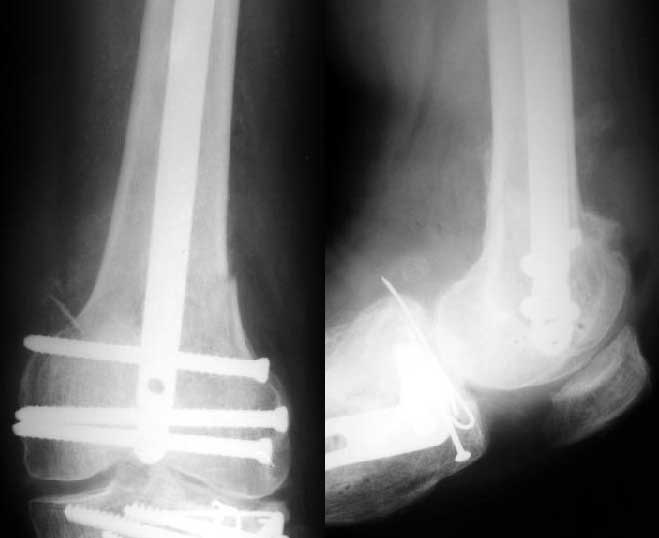

Отправитель: Alexander Chelnokov 27 Декабрь 2003, 21:34

Sorry but I've just prepared postop images - attached. A solid 13 mm nail was used. A few degrees of recurvation appears to be which i missed on image intensifier. I'm still uncertain about

advantages/disadvantages of ante/retrograde nailing for such fractures.

Отправитель: V.M.Iyer 27 Декабрь 2003, 21:36

The fixation as you have done is excellent. The locking screws on either side of the # are so apart. When we put in a supracondylar nail thro a keyhole incison in the knee, the locking bolts will be nearer the # and will be more stable allowing him to bear wt early. That was the reason the supracondylar nail was innovated. The locking is done by jig and no freehand method saving time.

the postop radiographs look excellent.

What do people think about driving an antegrade nail this distal as compared to retrograde nailing?

Those are all the arguments against retrograde nailing (surgical injury to the knee), but there are advantages like better distal fixation and control.

The antegrade nail in the case shown is probably into the knee joint slightly.

This case looks great but there must be some risk of splitting the condyles or other knee joint injury when driving an antegrade nail this distal. The antegrade nail also has entry site problems including variable injury to the hip muscles, heterotopic ossification, femoral neck fracture, and positioning difficulties. Overall the entry site problems seem about the same for the two techniques. If that is the case then the decision might come down to which one offers better distal fixation and that might be retrograde nail. If there are more entry site problems with retrograde nail than antegrade the antegrade nailing might be preferable even if the distal fixation isn't quite as good or reliable.

So, to me, it is a trade-off between benefits and risks for specific fracture patterns. In this case of a very distal femur shaft fracture the antegrade nail driven very distal in the femur looks extremely good. Without a comparative series we are left to base decisions on general principles, theory and related experience.